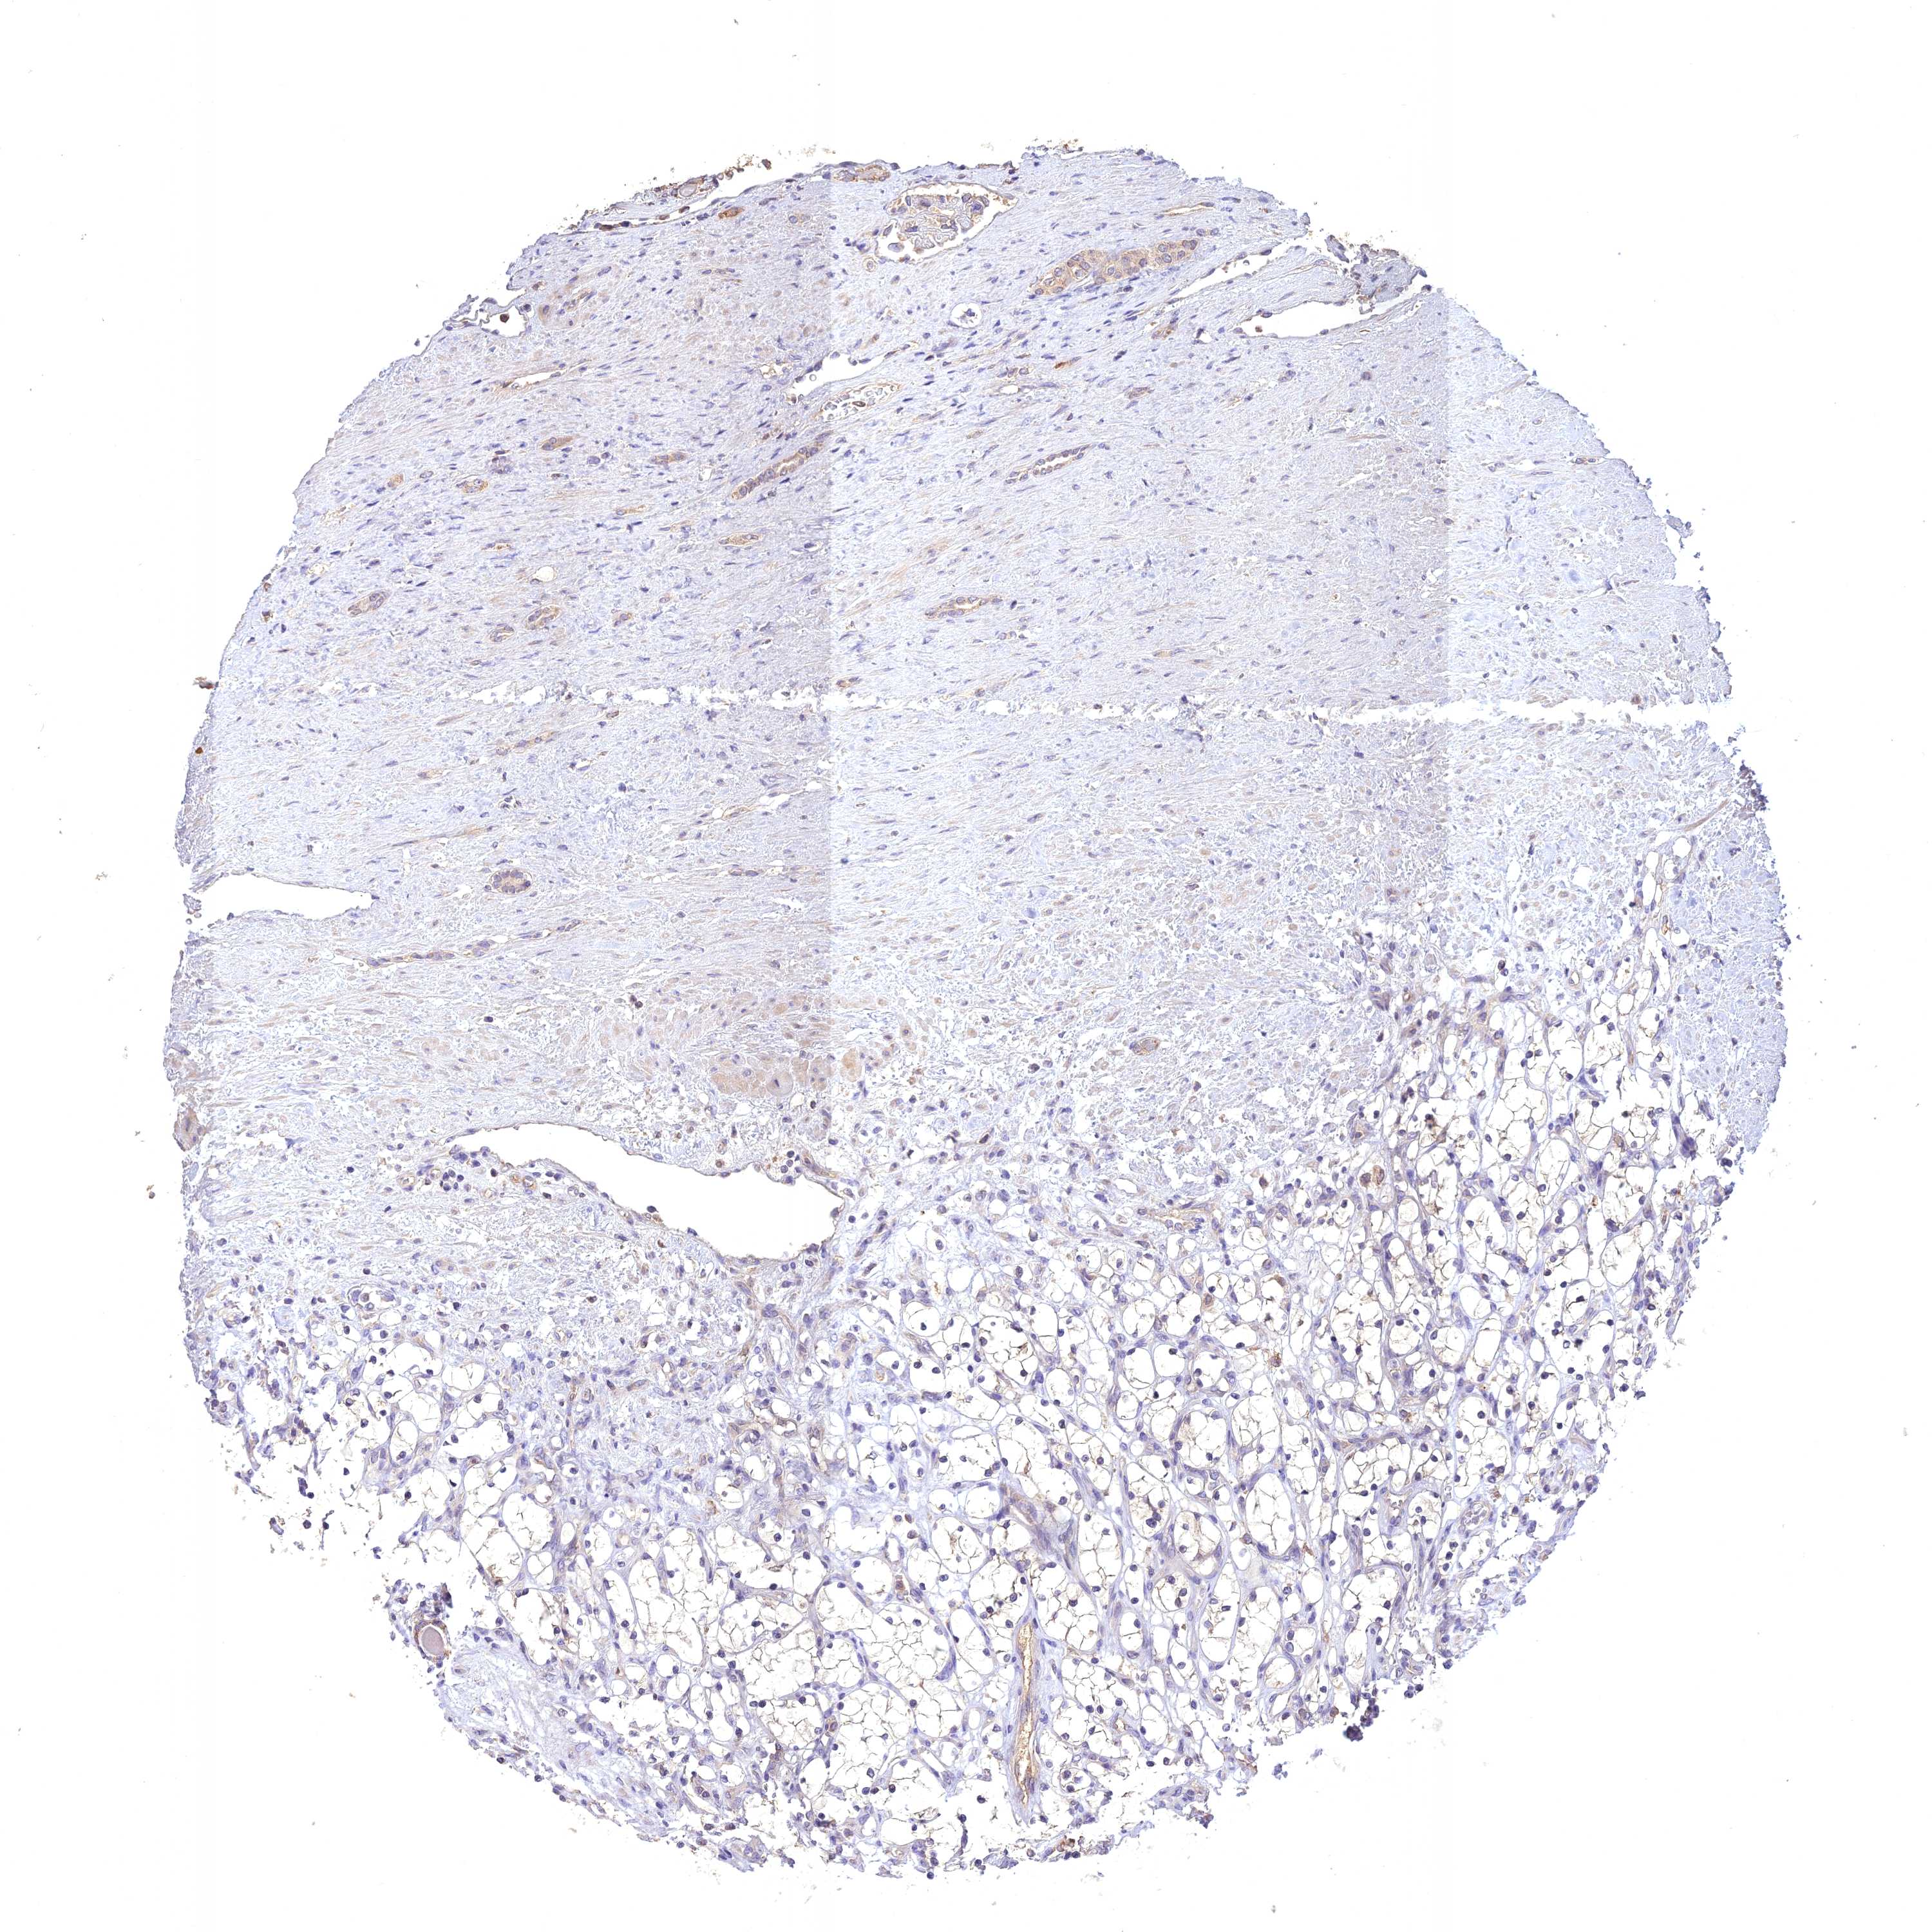

KIDNEY RENAL PAPILLARY CELL CARCINOMA (TCGA) - Interactive survival scatter ploti

The Survival Scatter plot shows the clinical status (i.e. dead or alive) for all individuals in the patient cohort, based on the same data that underlies the corresponding Kaplan-Meier plots. Patients that are alive at last time for follow-up are shown in blue and patients who have died during the study are shown in red.

The x-axis shows the expression levels (FPKM) of the investigated gene in the tumor tissue at the time of diagnosis. The y-axis shows the follow-up time after diagnosis (years). Both axes are complimented with kernel density curves demonstrating the data density over the axes. The top density plot shows the expression levels (FPKM) distribution among dead (red) and alive patients (blue). The right density plot shows the data density of the survived years of dead patients with high and low expression levels respectively, stratified using the cutoff indicated by the vertical dashed line through the Survival Scatter plot. This cutoff is automatically defined based on the FPKM cutoff that minimizes the p-score. The cutoff can be changed by dragging the vertical line or by entering a cutoff value in the square labeled "Current cut-off".

Under the Survival Scatter plot the p-score landscape (black curve; left axis) is shown together with dead median separation (red curve; right axis). Dead median separation is the difference in median mRNA expression between patients who have died with high and low expression, respectively. It is calculated as follows: median FPKM expression of dead patients with high expression - median FPKM expression of dead patients with low expression. This is intended to aid the user in visually exploring custom cutoffs and the associated p-scores and dead median separation.

Individual patient data is displayed and can be filtered by clicking on one or more of the category buttons on the top of the page. Categories describing expression level and patient information include: high, low, alive, dead, female, male and tumor stages. The scale of the x-axis can be toggled between linear and log-scale by clicking on the "x log" button. Mouse-over function shows TCGA ID, patient information and mRNA expression (FPKM) for each patient.

& Survival analysisi

Kaplan-Meier plots summarize results from analysis of correlation between mRNA expression level and patient survival. Patients were divided based on level of expression into one of the two groups "low" (under cut off) or "high" (over cut off). X-axis shows time for survival (years) and y-axis shows the probability of survival, where 1.0 corresponds to 100 percent.

NUDT8 is not prognostic in Kidney Renal Papillary Cell Carcinoma (TCGA)

Best expression cut offi

Based on the FPKM value of each gene, patients were classified into two groups and association between prognosis (survival) and gene expression (FPKM) was examined. The best expression cut-off refers the FPKM value that yields maximal difference with regard to survival between the two groups at the lowest log-rank P-value. Best expression cut-off was selected based on survival analysis .

When clicking on this number, the vertical dashed line indicating cut-off, the interactive survival plot, and the Kaplan-Meier curve will be adjusted to show results based on the best expression cut-off.

: 19.12

Median expressioni

Median expression refers to the median FPKM value calculated based on the gene expression (FPKM) data from all patients in this dataset. When clicking on this number, the vertical dashed line indicating cut-off, the interactive survival plot, and the Kaplan-Meier curve will be adjusted to show results based on the median expression.

: N/A

Median follow up timei

Median follow up time refers to the median time (years) after diagnosis with this type of cancer, based on clinical data from all patients in this dataset.

P scorei

Log-rank P value for Kaplan-Meier plot showing results from analysis of correlation between mRNA expression level and patient survival.

N/A

5-year survival highi

5-year survival for patients with higher expression than the expression cutoff.

For melanoma and glioma, 3-year survival is shown.

5-year survival lowi

5-year survival for patients with lower expression than the expression cutoff.

TCGA RNA samplesi

RNA-seq data is reported as average FPKM (number Fragments Per Kilobase of exon per Million reads), generated by the The Cancer Genome Atlas (TCGA) .

Normal distribution across the dataset is visualized with box plots, shown as median and 25th and 75th percentiles. Points are displayed as outliers if they are above or below 1.5 times the interquartile range. FPKM values of the individual samples are presented next to the box plot.

Average pTPM 25.4

Number of samples 282

Samples